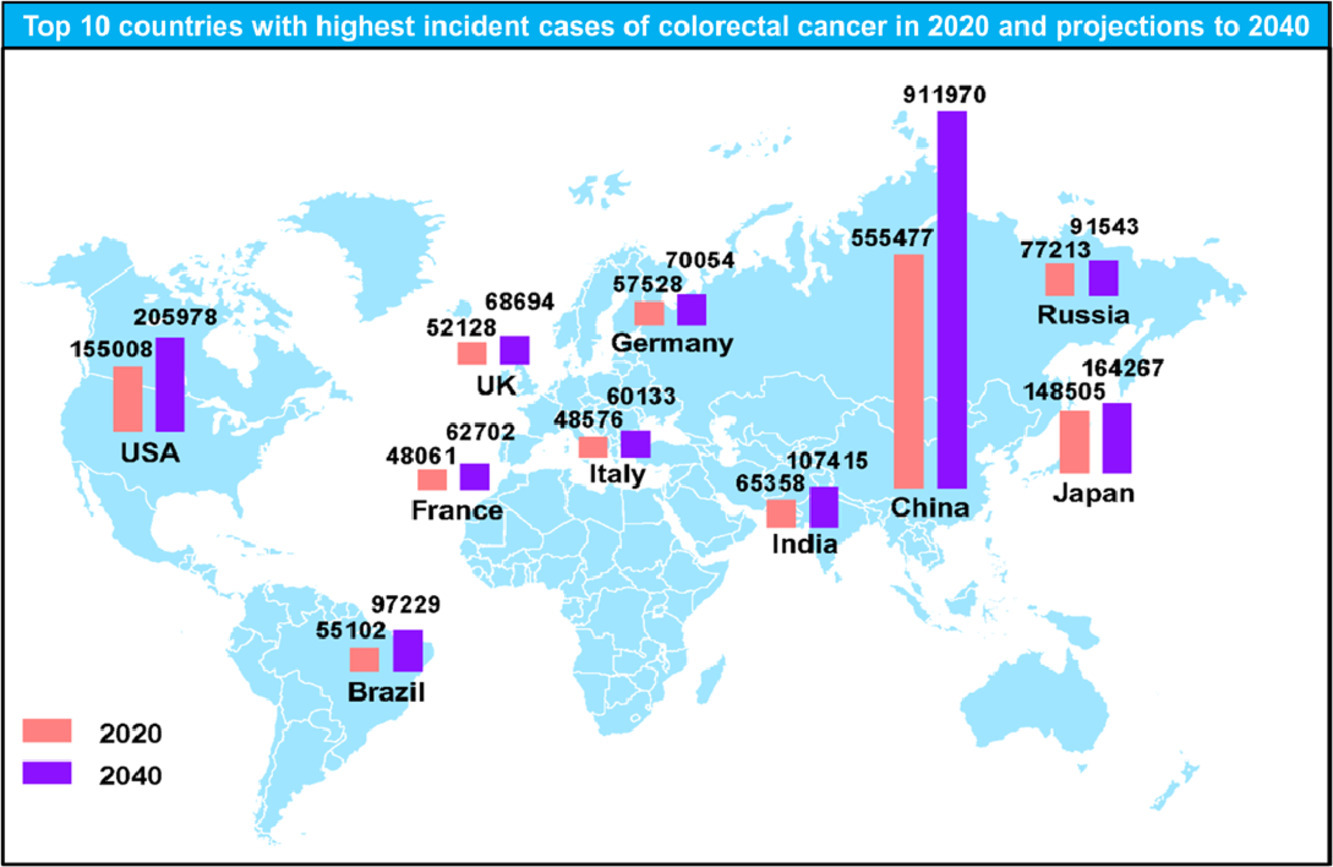

图1.2020年及2040年预测结直肠癌发病率最高的10个国家 [2]。

世界卫生组织国际癌症研究机构(IARC)发布的 2020 年全球最新癌症负担数据显示, 结肠癌是全球第五大常见癌症,2020 年全球新发病例数达 114.85 万,占所有癌症新发病例的 6.0%。 直肠癌是全球第八大常见癌症,2020 年全球新发病例数达 73.22 万,占所有癌症新发病例的 3.8%。 2020 年全球因结肠癌死亡人数约 57.69 万,占癌症死亡总数的 5.8%。 同年全球因直肠癌死亡人数约 33.9 万,占癌症死亡总数的 3.4% [1]。

近年来,中国大肠癌的发病率和死亡率均呈上升趋势。在我国恶性肿瘤发病中,大肠癌已位居第二。 2022 年中国大肠癌新发病例数约 51.71 万,其中男性新发病例数约 30.77 万,女性新发病例数约 20.94 万。 2020 年中国大肠癌死亡病例数约 24 万,其中男性病例数约 14.26 万,女性病例数约 9.74 万 [3]。